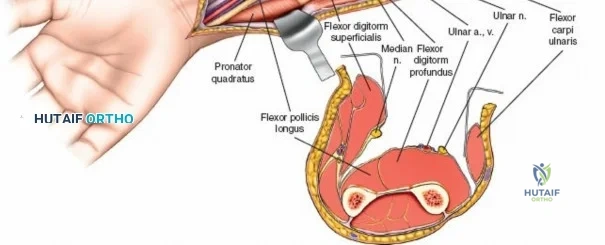

The Internervous Planes of the Forearm

The anterior approach to the radius is an elegant example of utilizing true internervous planes to achieve deep exposure without denervating musculature. Distally, the internervous plane lies between the brachioradialis muscle (innervated by the radial nerve) and the flexor carpi radialis muscle (innervated by the median nerve). Proximally, the plane transitions to lie between the brachioradialis (radial nerve) and the pronator teres muscle (median nerve). Exploiting this plane allows the surgeon to mobilize the entire lateral muscular compartment (the "mobile wad" comprising the brachioradialis, extensor carpi radialis longus, and extensor carpi radialis brevis) away from the anterior flexor compartment.

The Posterior Interosseous Nerve (PIN)

The posterior interosseous nerve is the single most important structure left vulnerable during exposure of the proximal radius. A branch of the radial nerve, the PIN dives into the supinator muscle through the Arcade of Frohse. It travels obliquely and spirally around the radial neck and proximal shaft within the substance of the supinator. In approximately 25% of patients, the nerve comes into direct contact with the posterior periosteum of the radial neck. Therefore, any blind placement of retractors around the posterior aspect of the proximal radius is strictly contraindicated, as it can easily crush the nerve against the bone, resulting in devastating loss of finger and thumb extension.

Exposing the proximal third of the radius requires extreme vigilance due to the proximity of the posterior interosseous nerve. The key anatomical landmark here is the insertion of the biceps tendon. Follow the biceps tendon distally to its insertion on the bicipital tuberosity of the radius. A small bursa lies just lateral to the tendon; incise this bursa to gain initial access to the proximal radial shaft. Because the radial artery lies superficial and medial to the tendon at this level, all deep dissection must remain strictly lateral to the biceps tendon.

The proximal radius is draped by the supinator muscle. The PIN passes directly through the belly of the supinator. To protect the nerve, the forearm must be fully supinated. Supination dynamically rotates the radius, carrying the insertion of the supinator anteriorly and simultaneously displacing the PIN laterally and posteriorly, safely away from the surgical field.